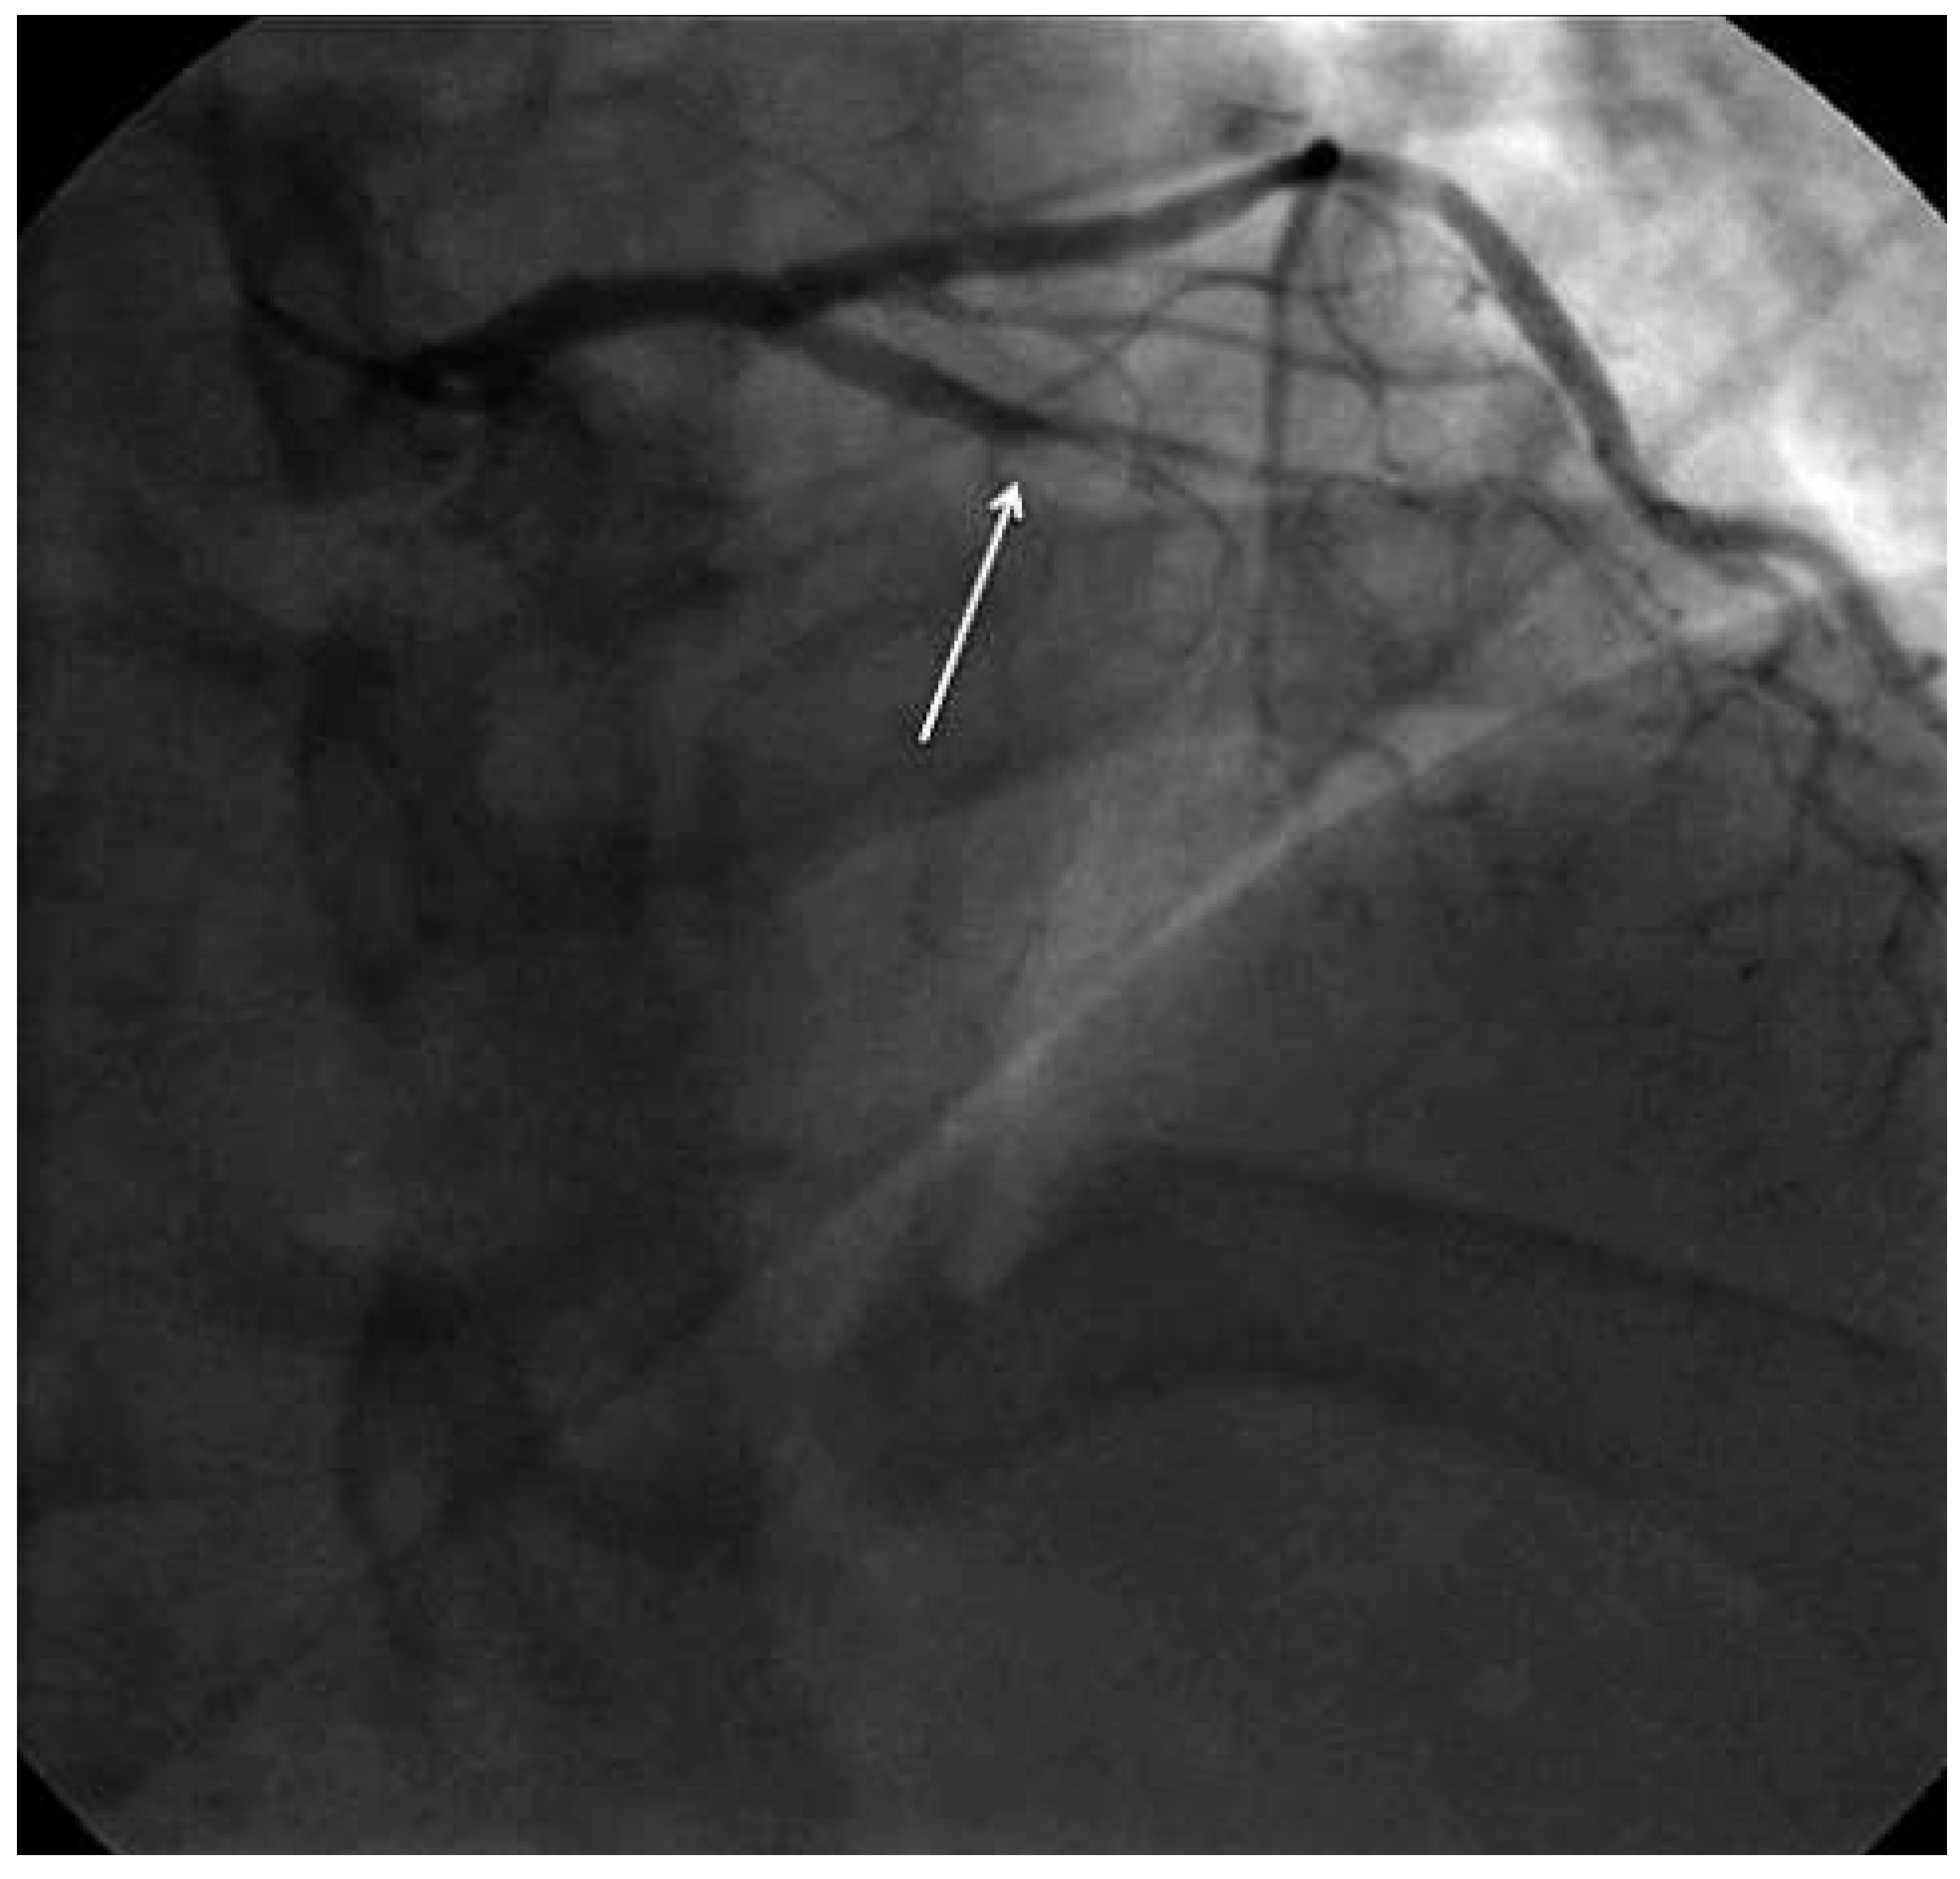

Case report